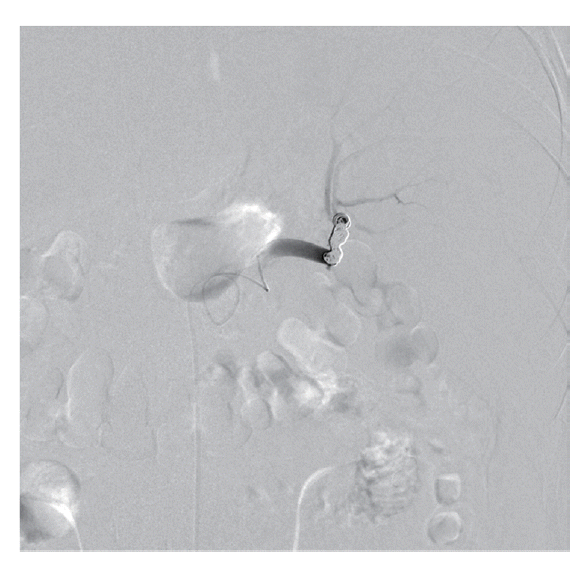

The patient’s hemoglobin level was 14.4 g/dl 1 day before visiting the Emergency Department and decreased to 11.0 g/dl. The concentration then rapidly dropped to 9.5 g/dl, and the patient received a blood transfusion. The patient also had thrombocytopenia (71 k/μl) with 33 IU/L AST, 44 IU/L ALT, 25.4 mg/dl BUN, and 1.66 mg/dl creatinine. He was admitted to the intensive care unit for a conservative treatment. Despite transfusion, the hemoglobin levels and blood pressure remained unstable. On the second day of hospitalization, a splenic angiogram was performed. No definitive extravasation of contrast media was observed, but contour irregularity was noted in the lateral lower margin (Fig. 3). Embolization was performed with 7 coils (10×4 mm, 8×4 mm, 6×2 mm; Cook, Bloomington, Minneapolis, USA) at the distal splenic artery level (Fig. 4).

Fig. 4.

Embolization was performed with 7 coils at the distal splenic artery level.

kjp-53-2-215f4.gif